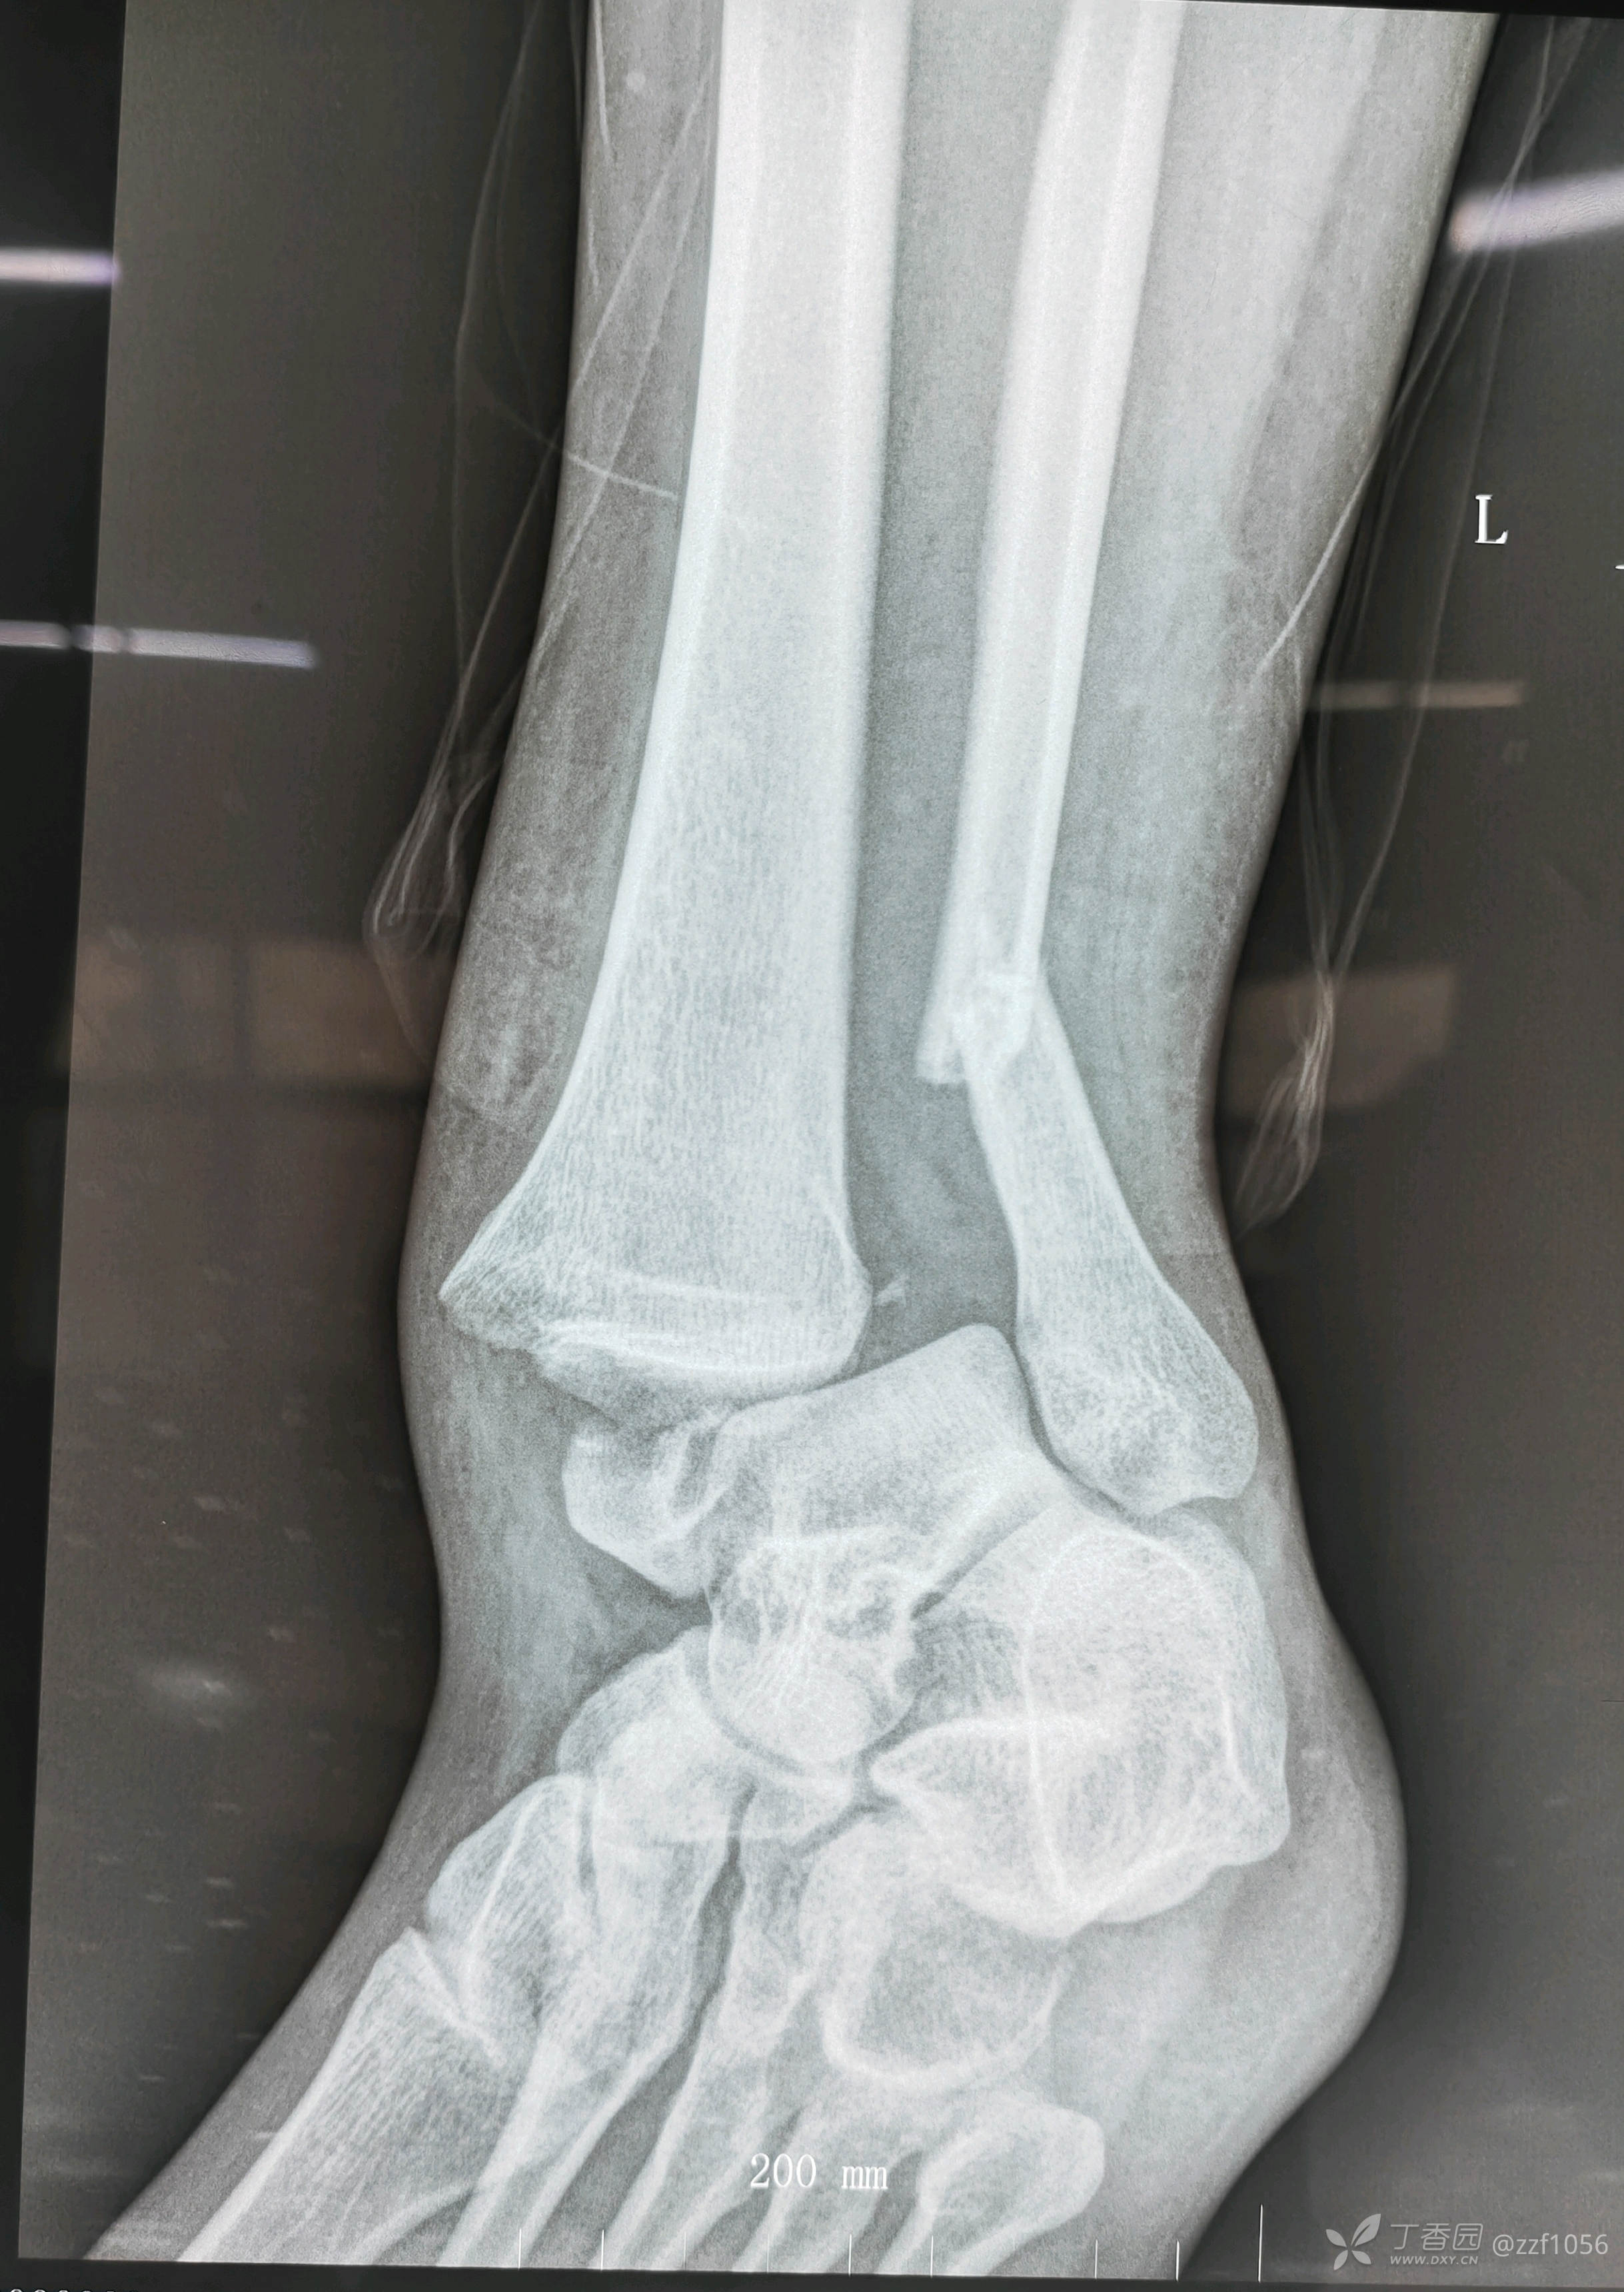

自诉8年前扭伤右踝致骨折,在某市三甲医院手术内固定治疗,而后右踝一直无法正常行走,右足点脚尖跛行。

入院诊断:右踝关节骨折术后畸形融合,内固定存留

从骨折畸形愈合形态应该能推测当时接近于劈木机损伤,旋前外旋四度骨折。

看一下目前CT